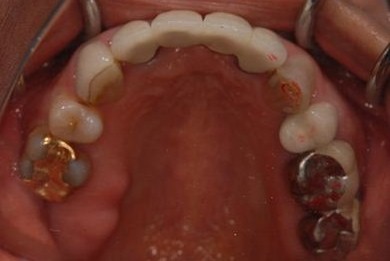

治療前

• 治療前